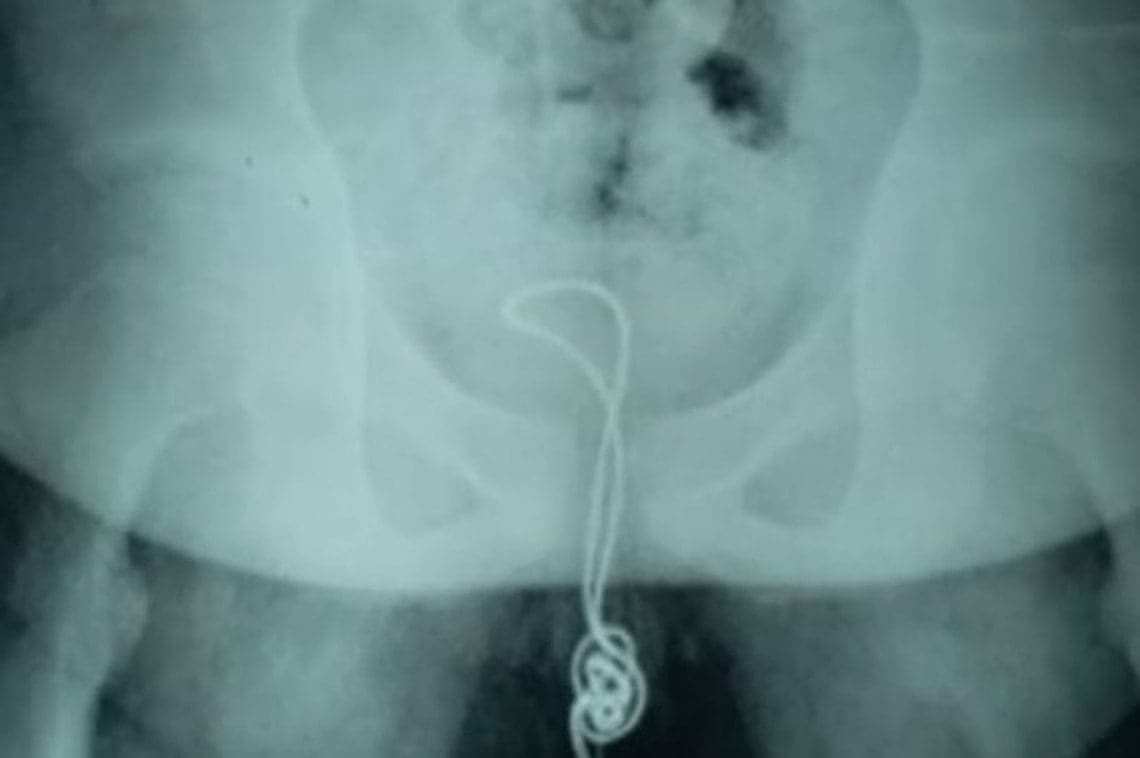

Tras revisar al joven que llegó por un dolor y hacerle una radiografía, los doctores encontraron un cable de carga en su estómago.

Procedimiento que les ayudó para extraerle al joven una cinta para el cabello y un cable de carga que alcanzó el metro de longitud cuando se estiró.

En declaración para medios locales, el médico explicó que el procedimiento no resultó sencillo, ya que el cable había pasado al intestino delgado.